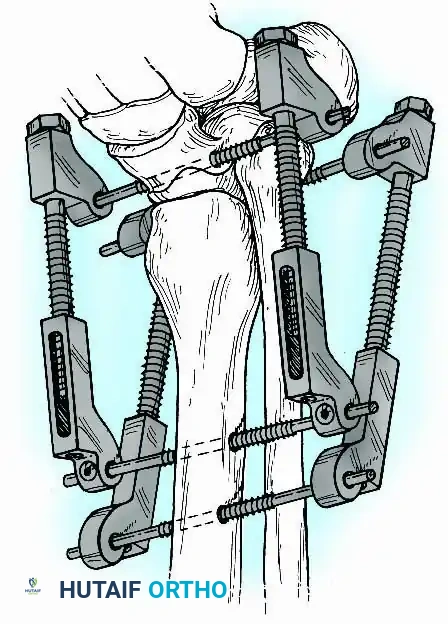

Historically pioneered by Charnley, external compression arthrodesis utilizes pins placed through the distal tibia and the body of the talus. Because Charnley's original uniplanar device lacked rotatory stability, Calandruccio designed a triangular frame to control motion in all three planes while applying massive compression.

Modern iterations, such as the Calandruccio II compression device, offer greater latitude in pin placement to avoid compromised skin. Ring or circular external fixators (Ilizarov, Taylor Spatial Frame) are the gold standard for salvage situations, including active infection, massive bone loss, or failed TAA, as they allow for simultaneous compression, deformity correction, and early weight-bearing.